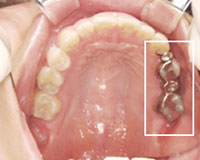

治療前

ブリッジ部分が虫歯になってしまった

2ケ所にブリッジがあります.